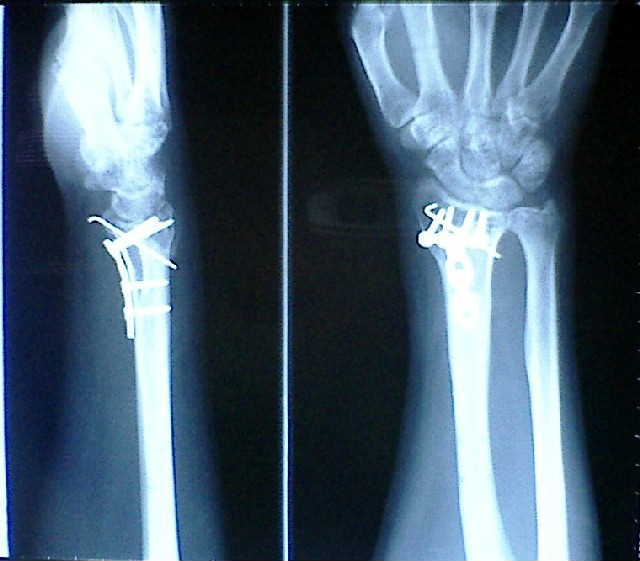

| 救急外来では、まずレントゲン撮影。画像を見ると、やっぱり骨折。と言うより砕けちゃってます。その上脱臼も。診断では、右橈骨遠位端骨折だそうです。その場で徒手整復を実施。早い話が、脱臼箇所を引っ張って直すんです。折れたところをそのまま引っ張るんですから痛いのなんのって・・・。その後、包帯状のギブスをして帰宅となりました。 | ||

| 12/14 | 手術 | 12時30分頃手術室へ。外来が長引いているため、しばらく待たされる。気を紛らすようにと、看護士さんが音楽をかけてくれる。 これから麻酔を入れますと言われたら、あっと言う間に意識が無くなってました。もっと眠気を感じるのかと思ってましたが、あまりにあっけなく。 あまりの痛さに目が覚めると、すでに手術の終わった後。それにしても痛い。 手術は手首の内側を切開し、折れた部分をプレートとピンで固定し、手首が動かないように外側に創外固定という金具を装着。まるでロボットアームのよう。 ストレッチャーからベッドに移されるとき、テレビでよくやってる「1・2・3!」ってのをやってもらった。衝撃もほとんど無く、上手いもんです。 一晩中、1時間ごとに作動する血圧計と痛みのため、うとうとしてもすぐに目が覚めてしまう。 |